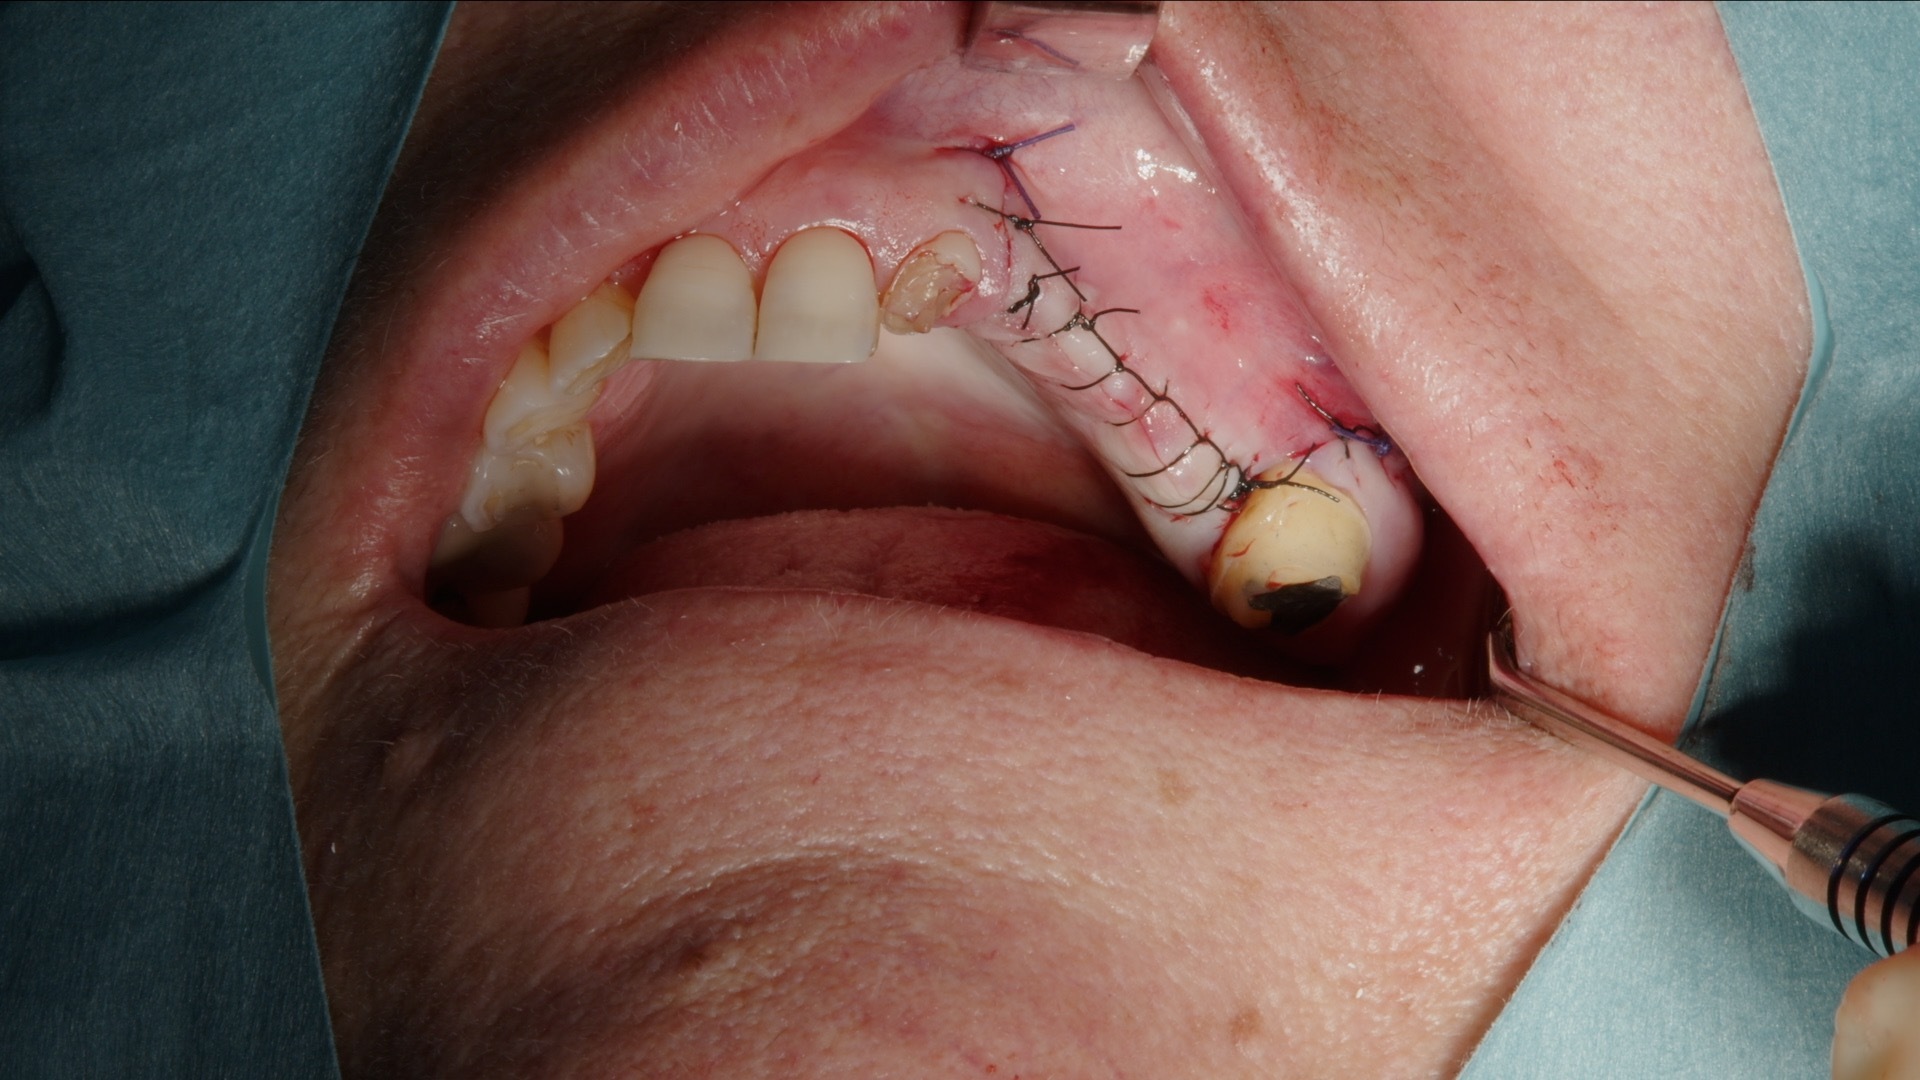

Efter utfyllnad täcks det laterala fönstret med Geistlich Bio-Gide kollagenmembran. Membranet fungerar som barriär mot mjukvävnadsinväxt och stabiliserar transplantatet under läkningsfasen. Därefter repositioneras lambån tensionfritt och sutureras noggrant.

7. Täckning av lateralt fönster med Geistlich Bio-Gide membran.

8. Suturering av lambå.